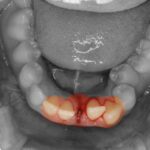

歯が抜けたり、折れたり、欠けてしまったら… 事故で大事な歯を失ってしまったら。「歯が無くなってしまった…」そのショックは...